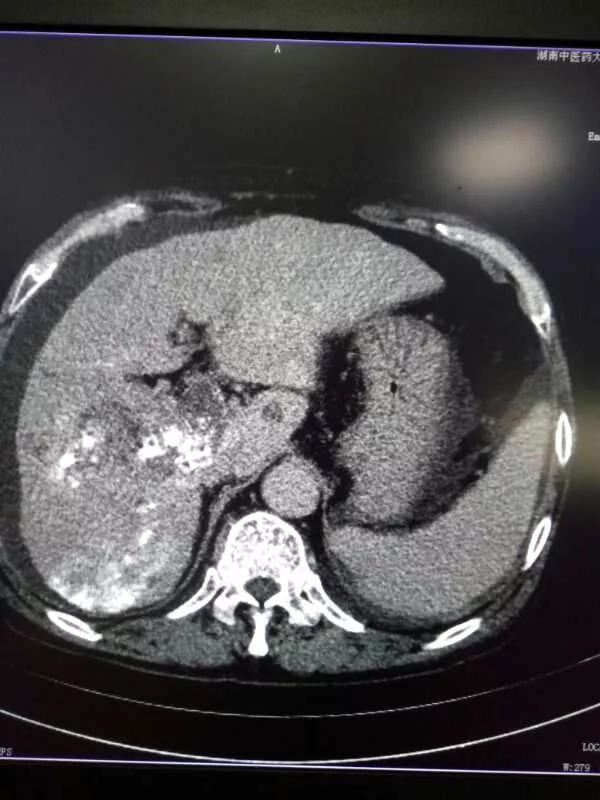

患者介入手术五天后复查CT和血液,效果明显:1、肝内原发癌灶和转移灶CT增强基本没有强化,提示病灶已经失去活性;2、门静脉癌栓缩小;3、检查肝癌最重要的生化指标AFP由术前的105降到现在的56。

术后: 肿瘤失去活性,AFP下降一半